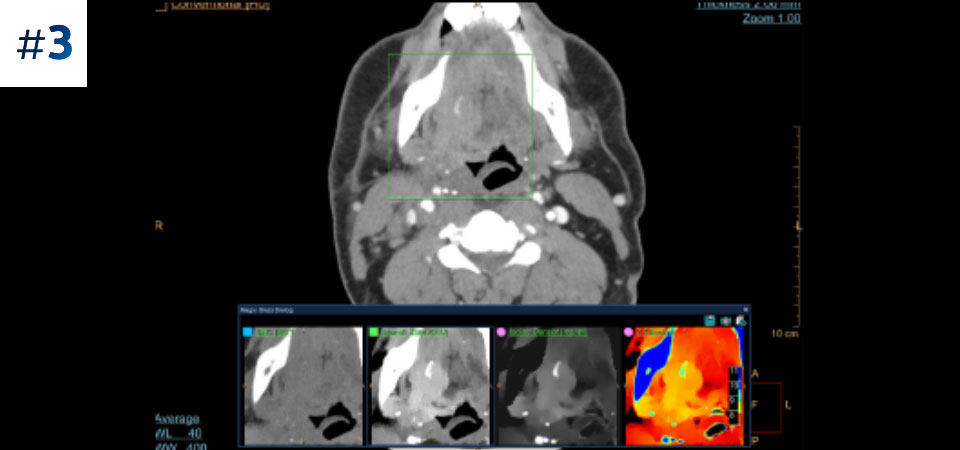

Nuestro CT con detección espectral de Philips, nos permite adquirir datos convencionales y espectrales en una sola exploración, sin cambios en nuestro flujo de trabajo actual.

Observe las diferencias entre un detector espectral CT y un CT Convencional

Aprenda sobre las ventajas del detector espectral CT